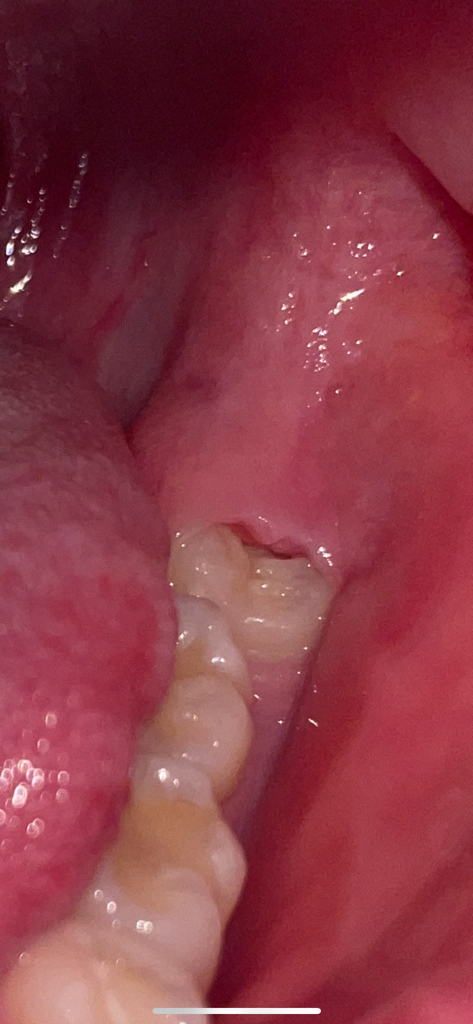

사랑니 잇몸이 벌어져있는데 자연치유 가능할까요?

사랑니 잇몸이 좀 벌어진거같아요.. 매일 치간칫솔로 안에 낀 음식물을 빼주는데요.. 사랑니 빼려면 한 한달 반 후에 뺄수있을거같은데ㅠㅠ 계속 치간칫솔 사용해줘도 될까요? 자연치유는 가능하나여..

• 1번 째 사진

해당 구멍으로 음식물이끼는 경우 치실이나 치간칫솔을 이용하여 제거를 하는 것이 좋습니다. 방치시에 잇몸에 염증이 생길가능성이 있기에 치과를 방문하여 사랑니 발치시기를 앞당기길 권합니다.

저건 잇몸이 벌어진게 아니라 사랑니가 부분적으로 맹출되서 그런겁니다. 자연적으로 치유가 되지는 않고 발치를 하시고 나면 잇몸은 아물게 될꺼에요.

저런 부분매복사랑니는 원래 문제를 일으킬 가능성이 많으므로 예방적발치가 권장되기도 합니다

다만 발치를 원치않는다면 사랑니를 덮고 있는 잇몸을 조금 잘라서(치은 절제술, 치은판개술) 구강위생관리가 좀 더 원활하도록 해줄 수 있습니다